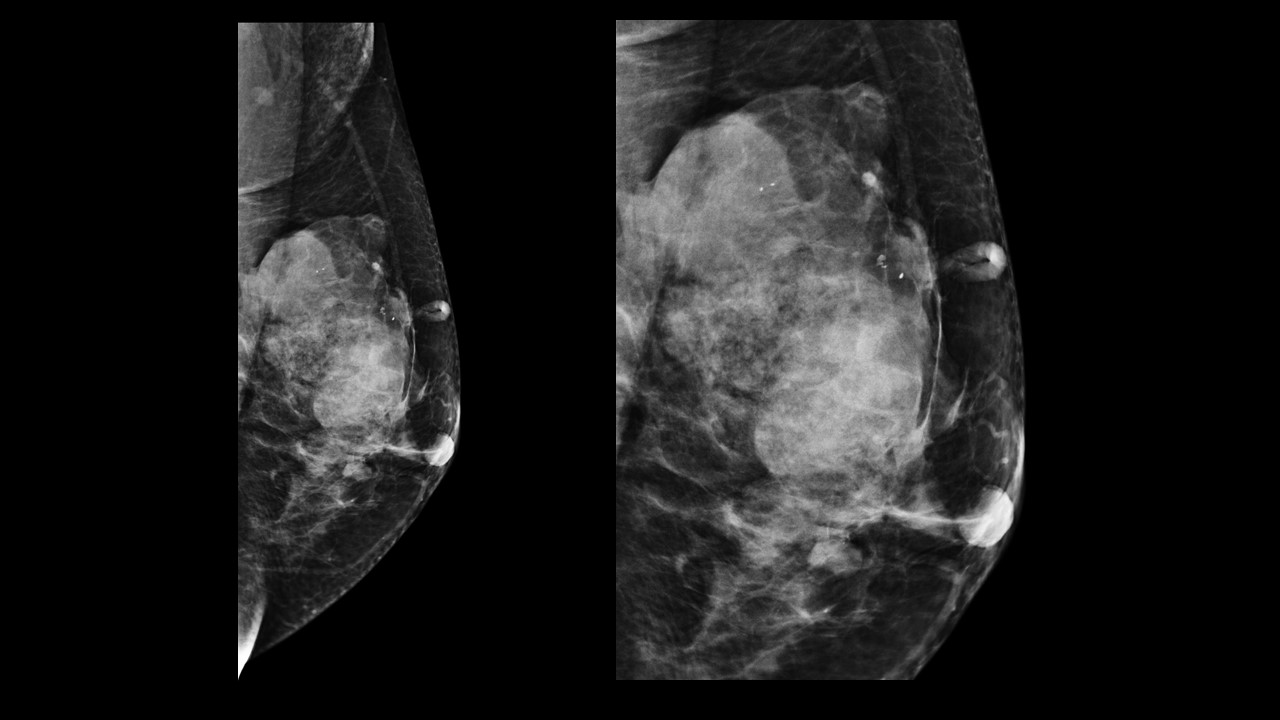

Physical examination revealed a 6.0?×?5.0 cm mass in the left breast. Mammography demonstrated an irregular, fat-containing, heterogeneous mass with circumscribed margins in the upper outer quadrant of left breast. Few scattered foci of coarse calcification were present within the mass. Breast sonography revealed an irregular, parallel, hyperechoic mass with circumscribed margins and no posterior acoustic features in the left breast at 3 o’clock position. Mild vascularity was observed on Color Doppler imaging. Contrast enhanced ultrasound (CEUS) done out of academic interest showed ill-defined, heterogenous enhancing mass, showing irregular shape, having surrounding vessels. Quantitative analysis showed higher PI (pulsatility index), AUC (area under curve) and lower TTP (time to peak) compared to normal tissue. The mass was assessed as Breast Imaging Reporting and Data System category 4b, and ultrasound-guided 14-gauge core biopsy revealed a biphasic tumor composed of bilayered ductal epithelium compressed by the proliferating stroma into leaf like architecture, The stromal cells showed increased cellularity, marked nuclear atypia and pleomorphism with round to oval nuclei, opened up chromatin, prominent nucleoli and moderate to abundant cytoplasm with many bizarre looking tumor giant cells. The stroma showed extensive heterologous lipomatous differentiation composed of neoplastic adipocytes as well as few lipoblasts. Mitosis was 3-4/10/hpf. Final histopathological diagnosis of malignant Phyllodes tumor with liposarcomatous differentiation was given. CT scan chest was done to look for lung metastasis, which revealed an irregular soft tissue mass in left breast with internal focal areas of fat attenuation. No nodules were seen in the lungs. Subsequent lumpectomy was performed and the gross specimen showed a well-demarcated tumor, measuring?6.8?×?6.5 × 3 cm. There were considerable bright yellow fatty components and some cleft-like spaces. Microscopically, the tumor exhibited a typical leaf-like growth pattern with extensive stromal overgrowth and stromal hypercellularity. Extensive areas of lipomatous differentiation were seen ranging from mature adipocytes to lipoblasts showing marked stromal atypia and irregularity. Mitotc activity was 7-8/10hpf. IHC for MDM2 was negative. Overall features were of malignant phyllodes tumor with well differentiated liposarcomatous differentiation.